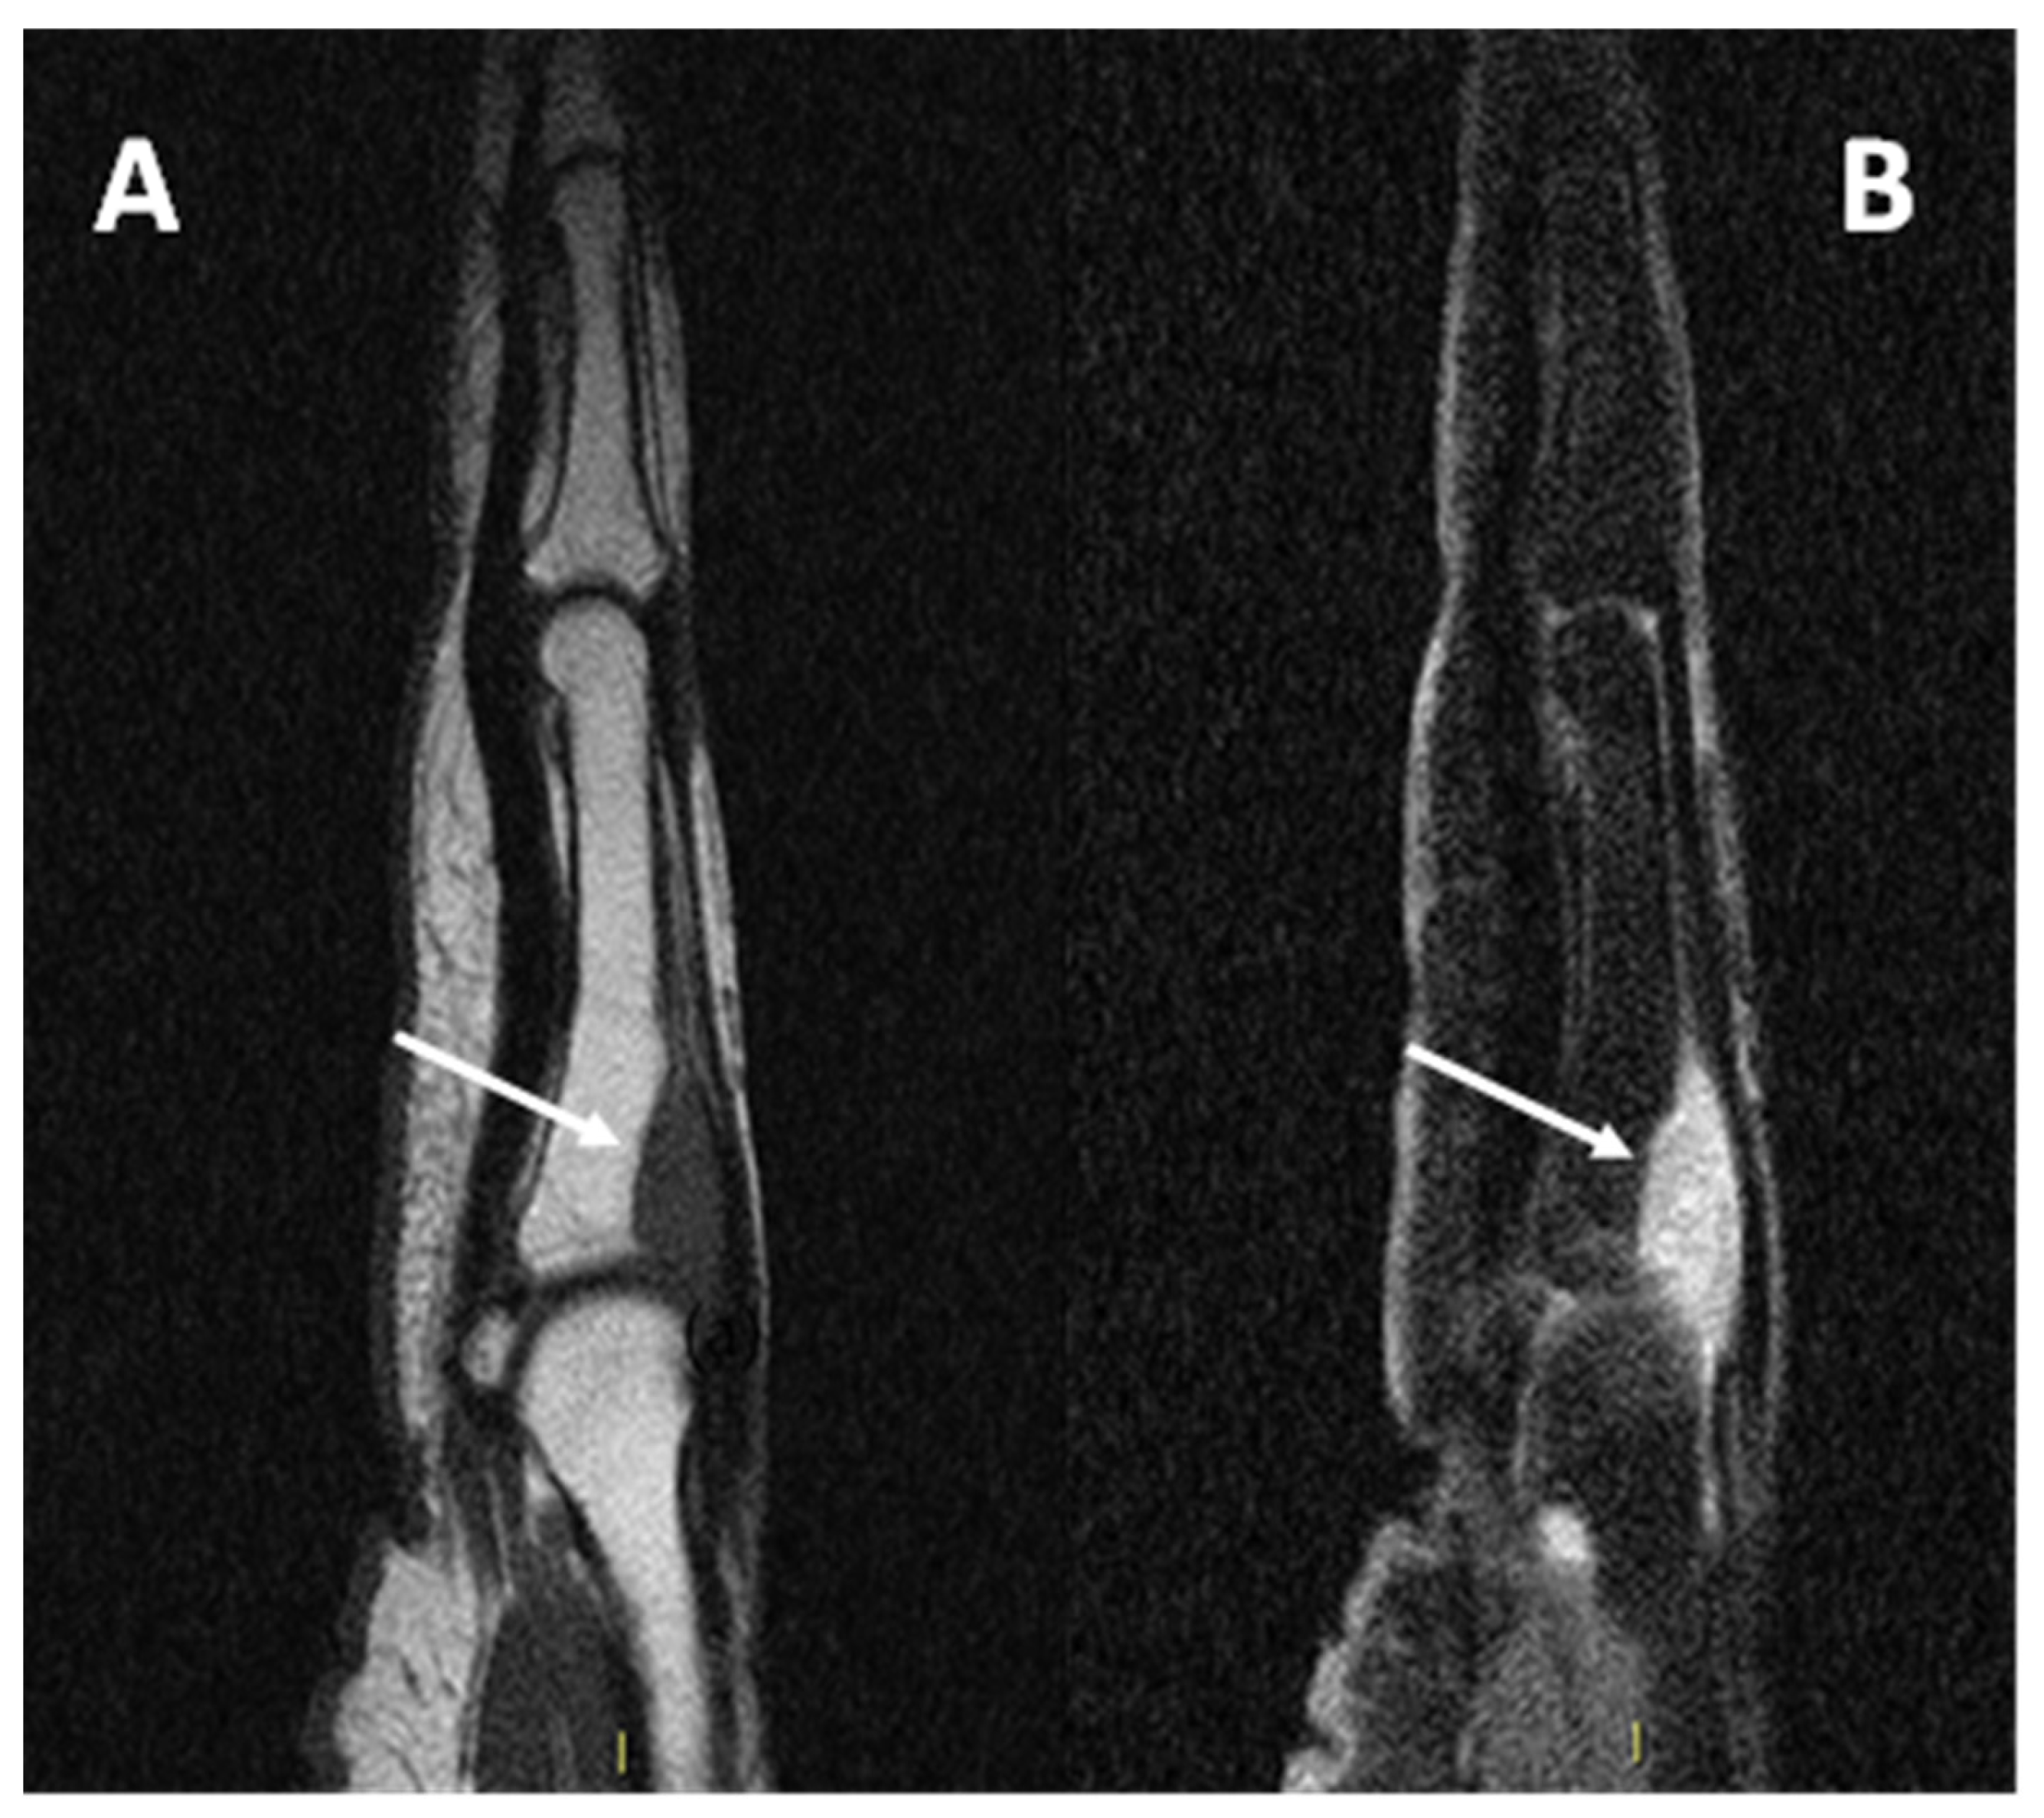

3.4. MRI Features

3.4.1. General MRI Features

3.4.2. Peritumoral Edema

3.4.3. Other MRI Features